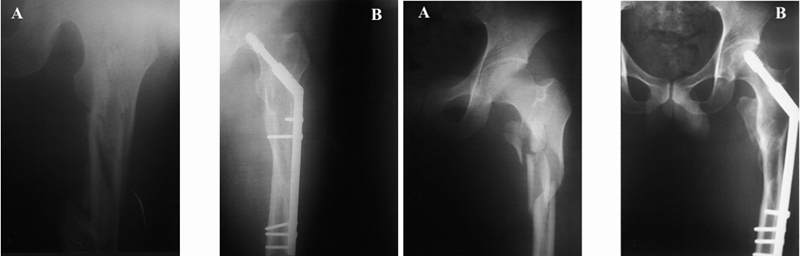

邓XX,男,56岁

术后8周